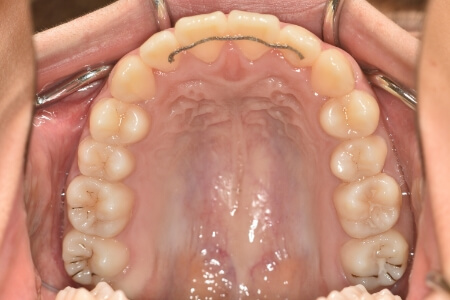

| 治療内容の詳細 | 初診時15歳の女性で、上の歯のがたつき、かみ合わせ、歯の中心のズレ、鼻から下が長いのを気にされ来院されました。 検査の結果、上顎前歯部叢生および開咬を伴うアングルⅠ級不正咬合と診断しました。 治療としては、非抜歯の上、マウスピース型矯正装置(インビザライン)で配列を行いました。顎間ゴムの協力もあり、開咬、中心のズレがきれいに改善されました。 治療期間は、2年でした。 |